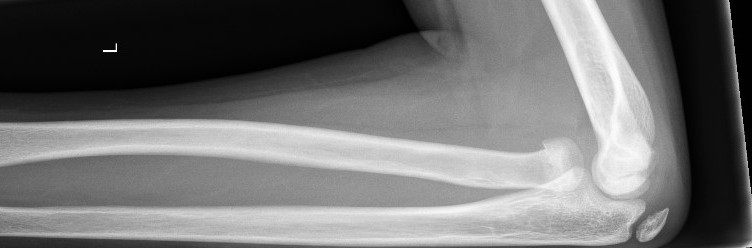

6. Look for obvious fracture lines on the AP view

|

Supracondylar fracture evident on the AP view |